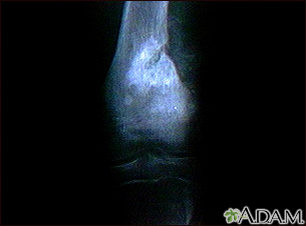

Osteogenic sarcoma - X-ray

This x-ray shows a malignant bone tumor (osteogenic sarcoma) of the knee. This type of tumor is usually seen in adolescents (around 15 years old). This tumor extends from the bone into the surrounding tissue.